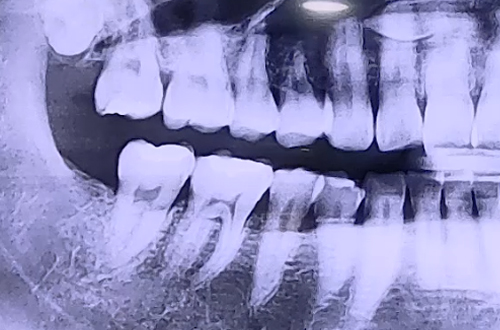

AFTER

이런 경우 금의 깊이가 머리부분까지로 깊지 않으면 신경치료 진행 후에

통증이 사라지면 크라운 치료로 마무리를 해 주게 되는데,

환자분께서는 뿌리 깊이까지 금이 가 있는 상태였기 때문에

당일 발치 후 임플란트 치료를 진행해 드렸습니다.

임플란트가 단단히 굳는 기간을 4개월 정도 기다린 후

어금니 보철이 완성되면 마무리 해 드릴 예정입니다. ^^